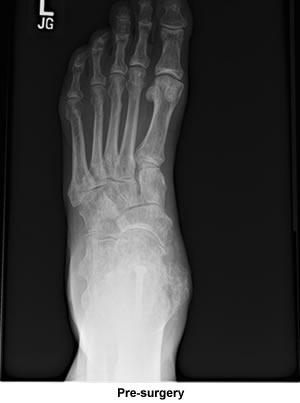

In 1994 after I moved to Cape Cod, my internist told me that he didn't see why I could not run with the fusion since he also had a foot fusion and was a runner. I would go to the high school track and run -- slowly one half a lap and then walk one half a lap. I continued doing this until my mile times were up to 8-minute miles. After a few short races I started getting pain again, so I gave up running completely again. The pain increased just with normal activities and reached the point where I needed more surgery.

I was all set to have the surgery done elsewhere on just one joint. Casually looking through the Cape Cod Times and spotting your ad for surgery on all sorts of foot problems and stating you were also available for consultation at your office in Bourne immediately convinced me to visit you as I did have some reservations about the surgery I was about to have. I figured that you would confirm that surgery, but that was not the case; you told me three joints were gone and needed fusions. You sent me a very convincing email and also fit me into your surgery schedule much sooner than normally would be expected because of your full workload. I just can't thank you enough for what your surgery has done for me.